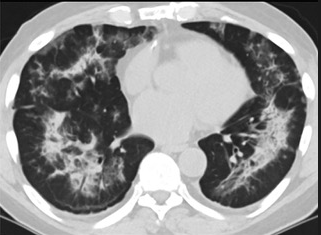

更值得注意的是,有之前应对过武汉新冠疫情的中国权威肺病专家,在查阅了60篇涉及美国“电子烟肺病”病例的研究论文,并对其中142位电子烟肺病患者的250张肺部影像图片、临床信息以及文献原文进行了仔细全面的研究后,发现这些病例中有16个更有可能是新冠肺炎的“疑诊患者”,有5个临床症状和治疗情况相对完整的患者,还被这些专家认定为了“中度可疑”。另外,这16个病例中有12个病例的发病时间,都在2020年以前。

(这4张图,是专家怀疑被误诊为电子烟肺病的其中一个病例的肺片。专家表示,他们不是仅仅通过一张影片做判断的,而是通过这4张涵盖了这名病例肺部多天变化情况的影片进行的研判,认为该病例的病程进展跟新冠更为相似)